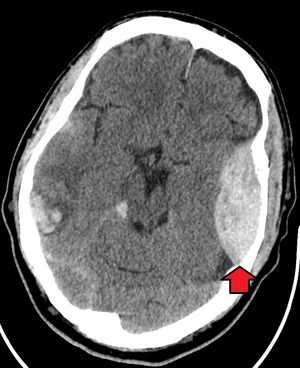

머리에 가해지는 둔기 외상은 주로 뇌 손상을 일으키며, 두개골, 얼굴, 안와, 목 등 다른 부위도 위험할 수 있다.[8] 환자의 기도, 순환, 호흡을 평가한 후, 목 부위 외상이 의심되면 목 깃을 착용할 수 있다. 두개 외상의 증거를 확인하기 위해 타박상, 좌상, 열상, 찰과상 등을 검사하고, 뇌 손상 여부를 평가하기 위해 신경학적 검사를 시행한다. CT 스캔은 두개골 내 출혈이나 두개골 뼈 골절을 평가하는 데 사용된다.[17]

외상성 뇌 손상(TBI)은 심각한 이환율과 사망률의 원인이며, 낙상, 자동차 사고, 스포츠 및 업무 관련 부상, 폭행으로 인해 가장 흔하게 발생한다. 특히 25세 미만 환자 사망의 가장 흔한 원인이다. TBI는 경증에서 중증까지 등급이 매겨지며, 심각도가 높을수록 이환율과 사망률이 증가한다.[17][18]

심각한 외상성 뇌 손상을 겪는 환자는 미만성 축삭 손상, 뇌 타박상, 지주막하 출혈, 경막하 혈종, 경막외 혈종, 뇌실질 내 출혈 등 다양한 뇌내 손상을 겪을 수 있다.[8][17] 뇌 기능 회복은 뇌내 손상에 따라 다르지만, 초기 손상의 심각성과 신경 기능 수준, 지속적인 신경 결손 수준 사이에 상관관계가 있다.[17] 초기 치료는 두개 내압을 감소시키는 것을 목표로 할 수 있으며, 반두개 절제술과 같은 수술이 필요할 수 있다.[8][17]

머리 둔기 외상의 경우, 두개골 및 뇌 CT 스캔을 통해 두개 내 출혈이나 두개골 골절 여부를 확인한다.[17]